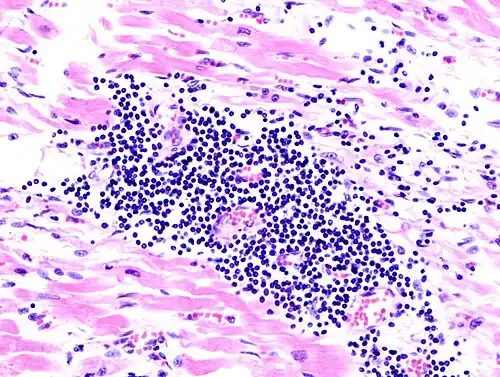

Surgical pathology is the most significant and time-consuming area of practice for most anatomical pathologists. Surgical pathology involves gross and microscopic examination of surgical specimens, as well as biopsies submitted by surgeons and non-surgeons such as general internists, medical subspecialists, dermatologists, and interventional radiologists.

The practice of surgical pathology allows for definitive diagnosis of disease (or lack thereof) in any case where tissue is surgically removed from a patient. This is usually performed by a combination of gross (i.e., macroscopic) and histologic (i.e., microscopic) examination of the tissue, and may involve evaluations of molecular properties of the tissue by immunohistochemistry or other laboratory tests.